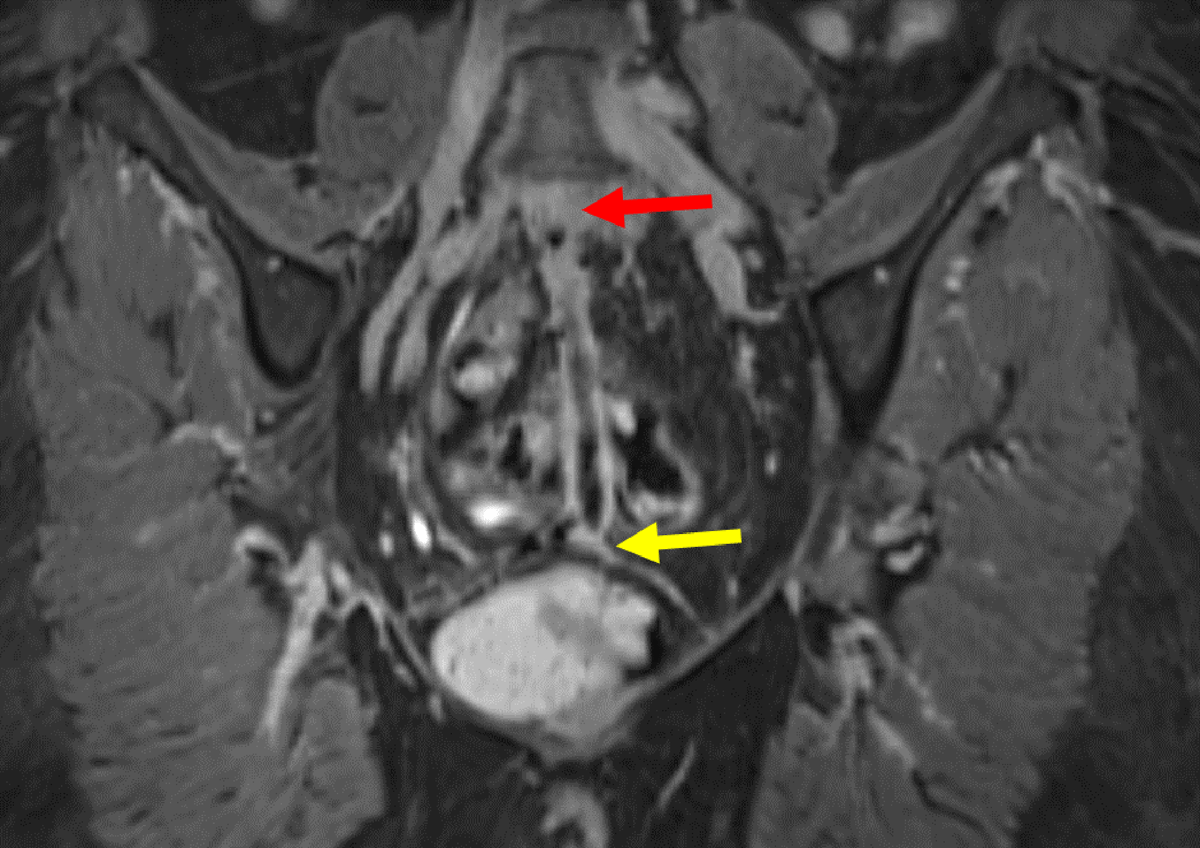

Figure 6

Coronal 3D contrast MRI in T1 fat saturation weighing: Full path of fistula from L5-S1 (yellow arrow) to the vagina (red arrow). The fistula presents with a hyperintense wall surrounding a hypointense lumen.